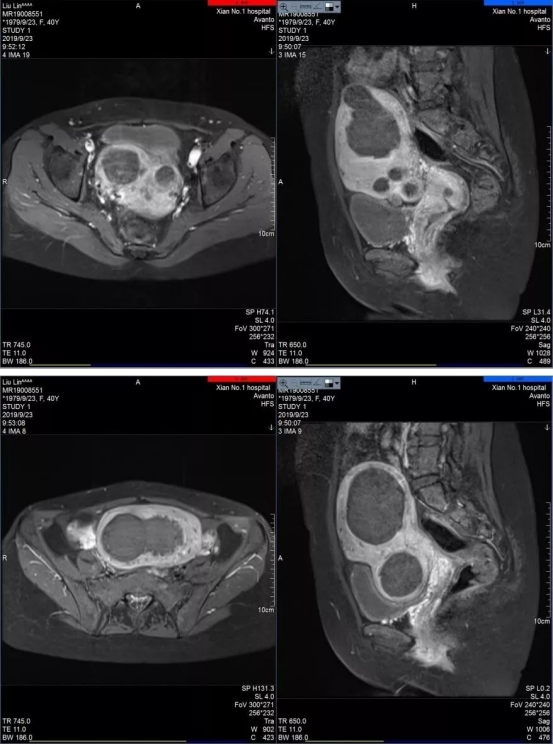

海扶刀治疗再创佳绩!成功完成一例多发性子宫肌瘤合并子宫腺肌症患者的海扶消融